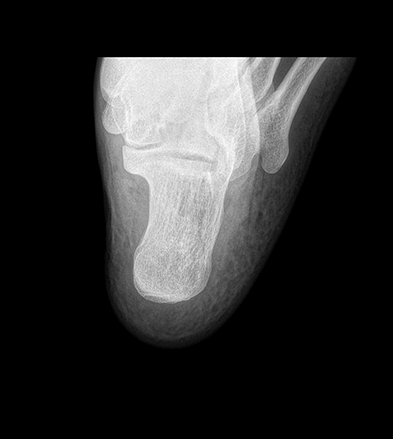

平板探测器

超大尺寸

超范围

超高像素

高清点片